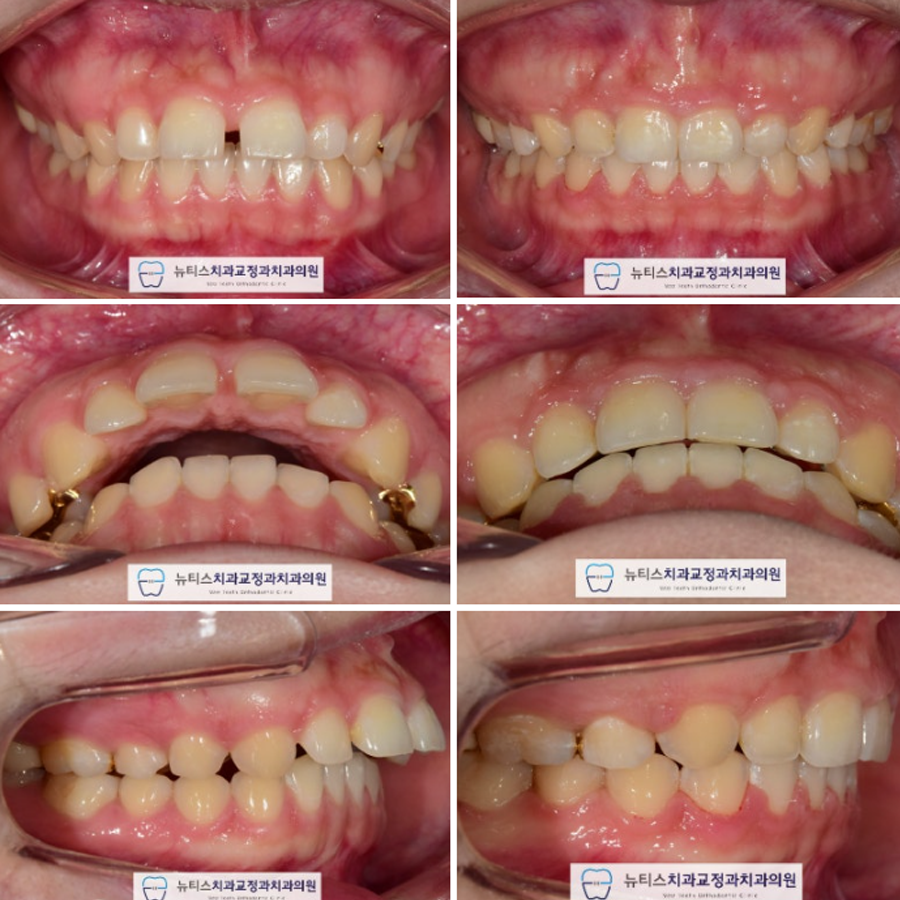

ÀåÄ¡ Á¦°Å ÈÄ »çÁøÀÔ´Ï´Ù.

°¡Áö·±ÇÑ Ä¡¿°ú ÇÔ²² °³¼±µÈ

±³ÇÕÀ» È®ÀÎÇÒ ¼ö ÀÖ½À´Ï´Ù.

Àü ÈÄ ºñ±³ »çÁøÀÔ´Ï´Ù.

ÃÊÁø¿¡ ºñ±³½Ã Ä¡¾Æµ¹ÃâÀÌ ÇØ°áµÇ¾ú°í

±³ÇÕ°ü°è°¡ °³¼±µÇ¾ú½À´Ï´Ù.

¶ÇÇÑ ÀÌÀü¿¡ ¾Õ´Ï·Î À½½ÄÀ» ¸Ô±â Èûµé¾ú´Âµ¥

Áö±ÝÀº ¸éµµ Àß ²÷¾î¼ µå½Ê´Ï´Ù~